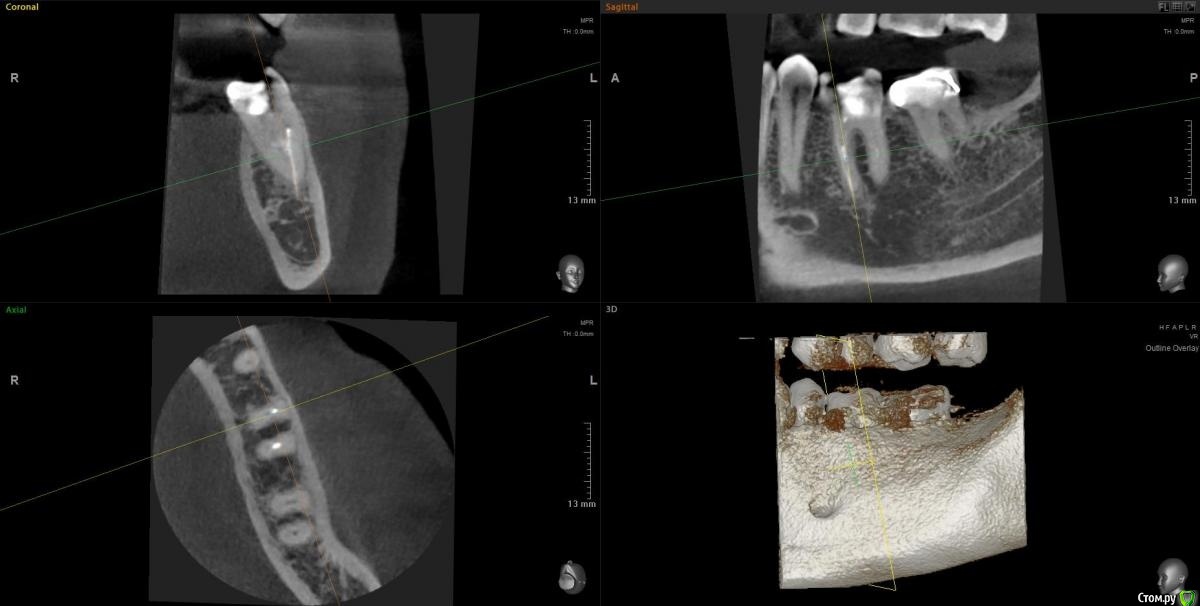

Slava76 Опубликовано 7 декабря, 2020 Автор Поделиться Опубликовано 7 декабря, 2020 (изменено) Сегодня сделал КТ. Выложил здесь https://cloud.mail.ru/public/2ezX/2HwT6HocyНа вечер записался к другому врачу. Послушаю, что он скажет.До обеда при нажатие была небольшая боль. Сейчас практически ее не чувствую. И так уже 4 дня. P.s.1 очень боюсь начать лечить не тот зуб. Коронку очень не хочется трогать. Ей все два года. Делала ее очень хороший врач.P.s.2 может само все пройдет... Изменено 7 декабря, 2020 пользователем Slava76 Ссылка на комментарий

Slava76 Опубликовано 7 декабря, 2020 Автор Поделиться Опубликовано 7 декабря, 2020 Вернулся от врача. Он посмотрел КТ и подтвердил слова DmitrySH. На 90% врач уверен, что проблема из-за не до конца залеченного канала и сломанного инструмента. Сказал, что нужно лечение под микроскопом. У них в поликлинике таких специалистов нет. Завтра начну искать такого врача в Нижнем Ссылка на комментарий

wladdX Опубликовано 7 декабря, 2020 Поделиться Опубликовано 7 декабря, 2020 (изменено) Трещины в зубе 37 не увидел Изменено 7 декабря, 2020 пользователем wladdX Ссылка на комментарий

Slava76 Опубликовано 8 декабря, 2020 Автор Поделиться Опубликовано 8 декабря, 2020 (изменено) Трещины в зубе 37 не увидел Значит однозначно "виноват" зуб с пломбой. Буду перелечивать каналы (если найду, кто вытащит сломанный инструмент) и ставить коронку.Звонил сейчас в одну из клиник, говорят вместо микроскопа используют специальные очки. С ними реально вытащить сломавшийся инструмент? Изменено 8 декабря, 2020 пользователем Slava76 Ссылка на комментарий